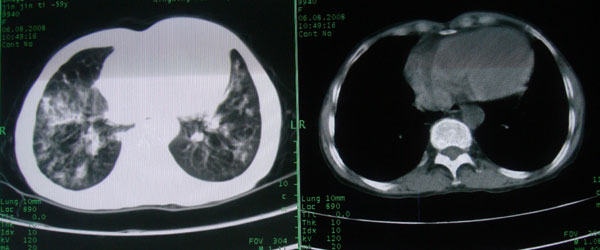

多考虑支气管扩张并感染,双下肺继发性肺结核不除外

周围型肺癌征象不明显,应不予首先考虑

慢性支气管炎伴支气管扩张\\感染.

考虑支气管肺泡癌可能性大

慢性支气管炎伴支气管扩张、感染,间质纤维化。